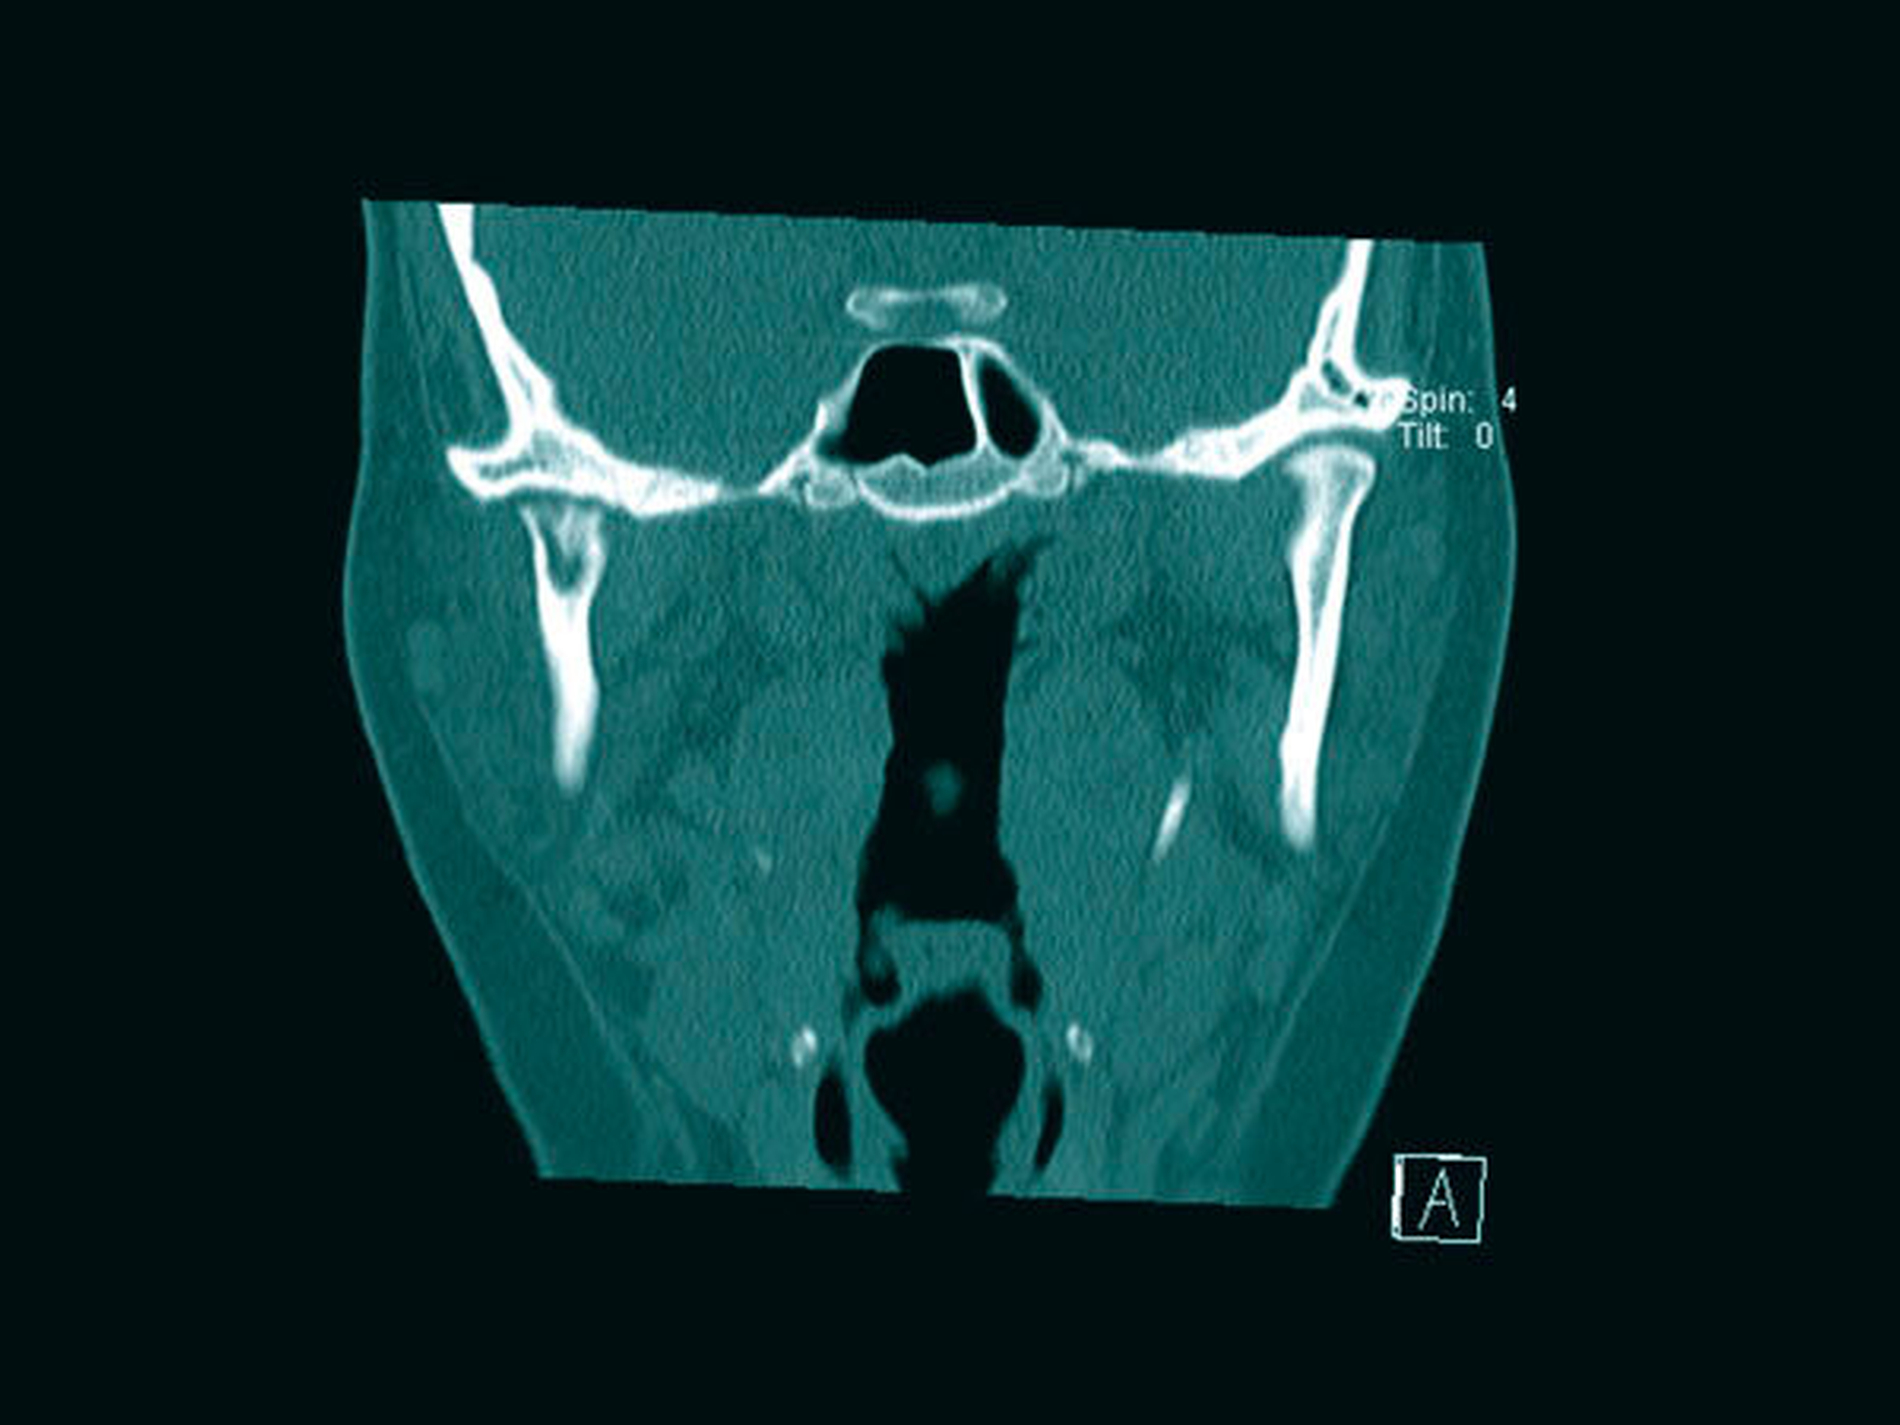

Aufgrund einer erneuten starken Zunahme der Beschwerden 2018 war der Leidensdruck der Patientin nach drei Jahren nun so groß, dass sie nach Bestätigung der erneuten Aktivitätszunahmen im Bereich des Capitulums in der Knochenszintigrafie und einer erneuten Osteolyse und in der CT im Bereich des aufsteigenden Unterkieferastes rechts und des Capitulums die Planung eines total-endoprothetischen Kiefergelenkersatzes wünschte (Abbildungen 8a bis 8c).